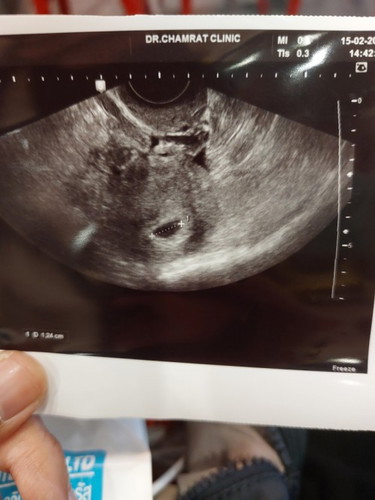

แม่ๆเจอลูกตอนกี่วีคค่ะ เราพบแต่ถุงไม่พบเด็ก 8 วีคแล้ว กลัวท้องลมมากเลยค่ะ

แม่อาจไข่ตกช้านะคะ ดูจากรูปเหมือนแค่5วีค เจอแต่ถุงตั้งครรภ์